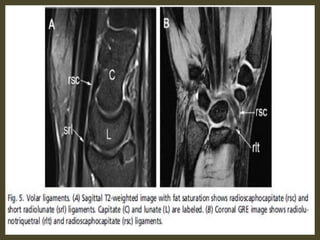

Triangular fibrocartilage complex tear.

Acute TFCC tear on FS T2-WI (A) and T1-WI (B).

TFCC 1B tear (arrow) on coronal T1-WI (B) and coronal FS T2-WI (C).